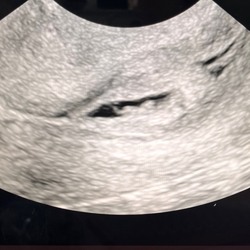

Vandaag zou ik 6 weken en 1 dag zwanger zijn. Er was al te zien dat het vruchtje niet op de juiste plek zat dit in de baarmoederhals ipv boven in de baarmoeder. Ook zou de vruchtzak niet mooi rond zijn en eerder platgedrukt. Dokters vertelde ons dat dit een miskraam zou worden,toch sinds gisteren hart activiteit te zien en te horen.

Vanmiddag verloor ik dit ( zie foto ) is dit mijn miskraam? Voelt niet ‘hard’ aan. Verder geen buikpijn krampen of verder bloedverlies.